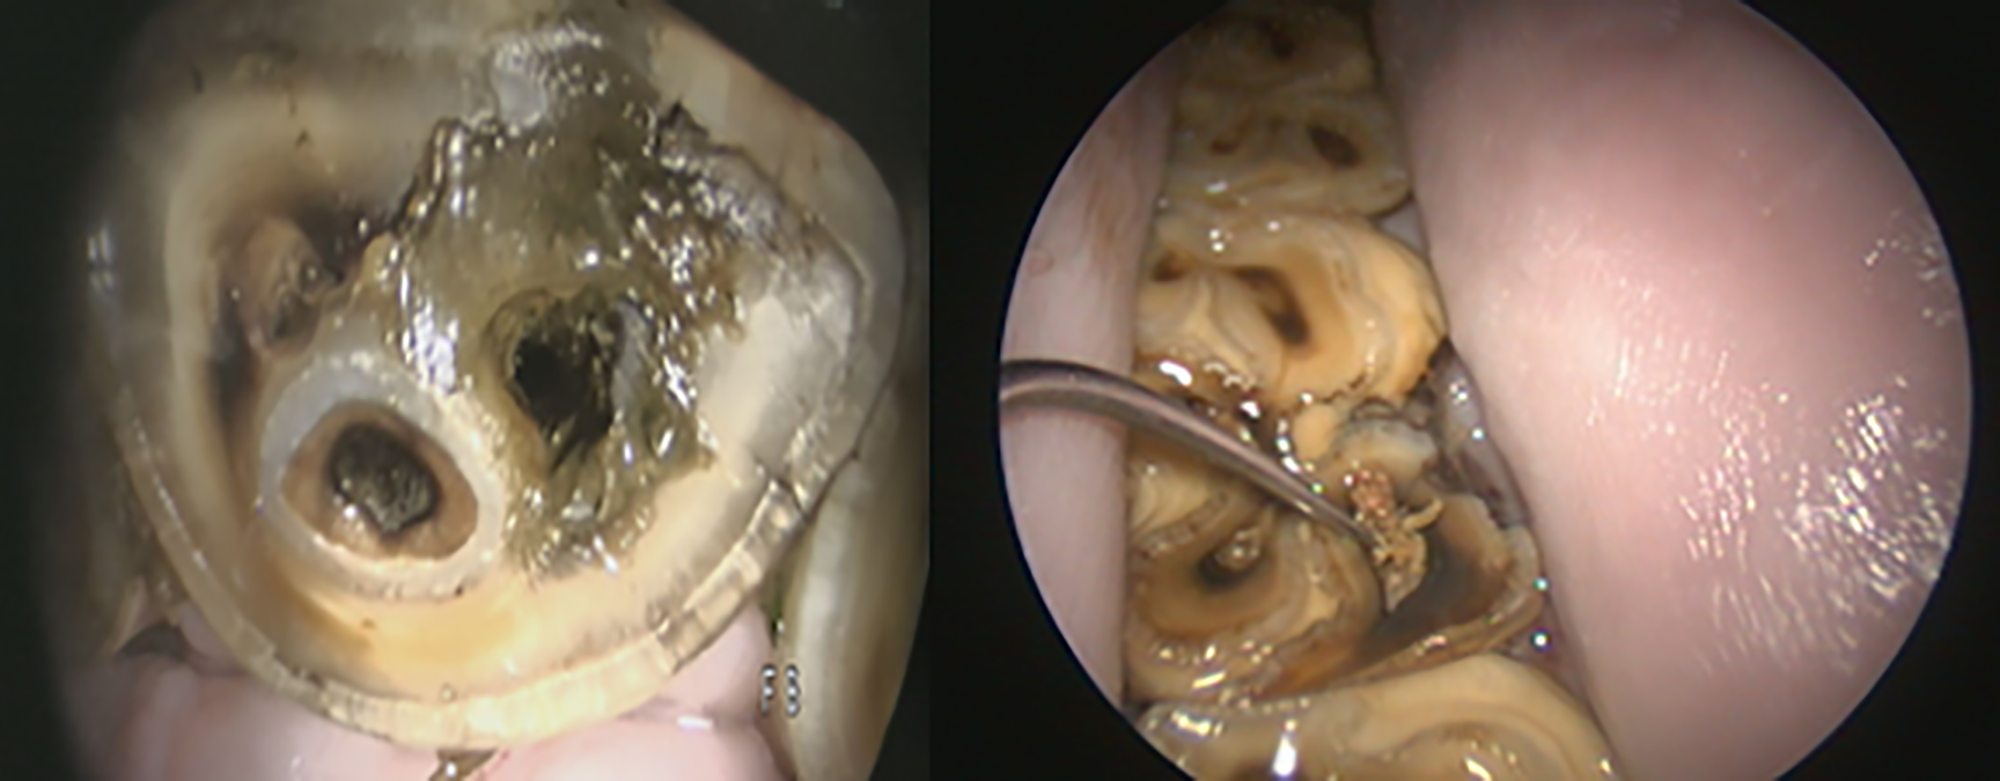

Dentine defects on the surface of an incisor and lower mandibular cheek tooth with associated food contamination and chronic endodontic infections. Credit: John Mark O’Leary MRCVS